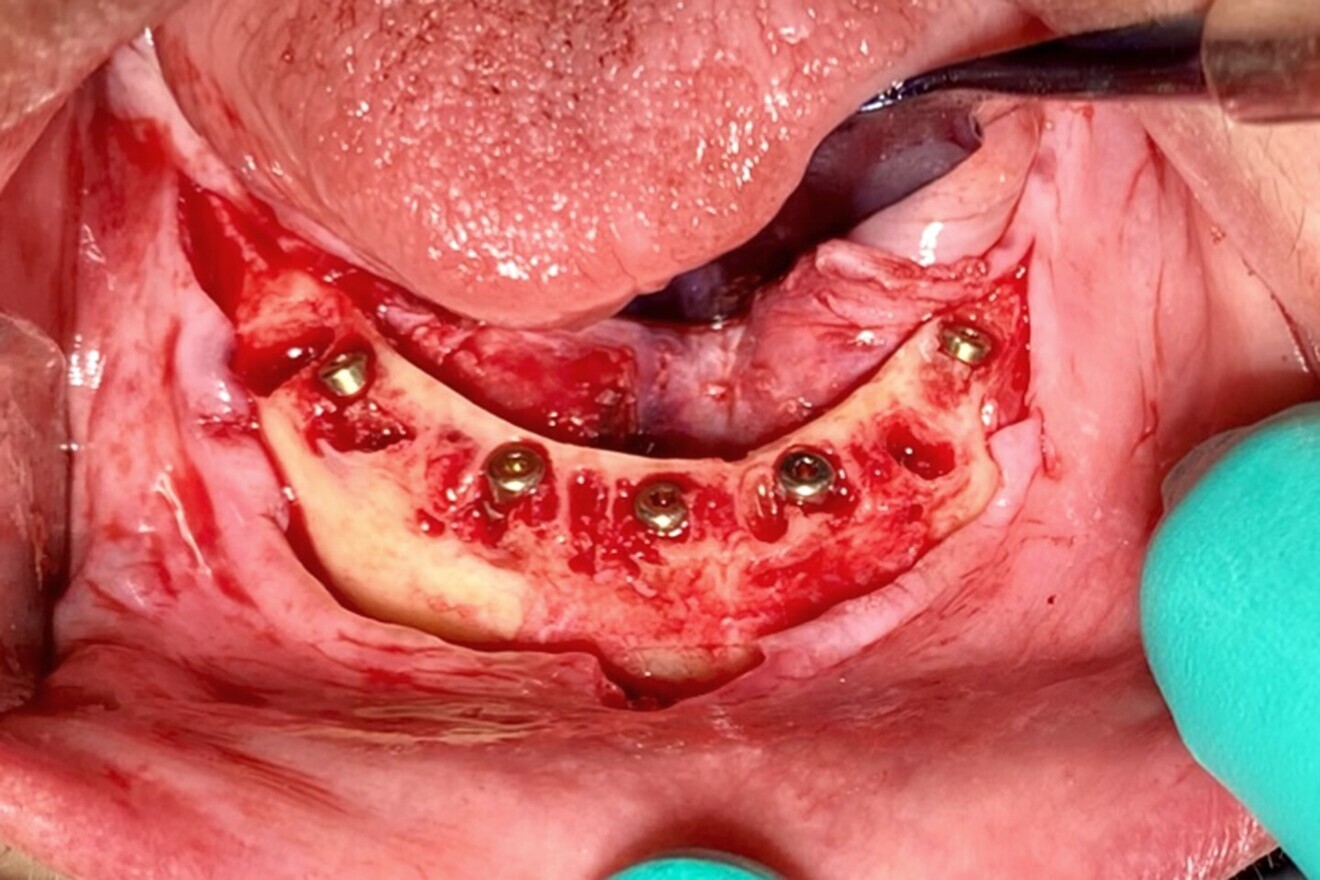

Each implant was then objectively tested for stability using resonance frequency analysis, and implant stability quotient (ISQ) values were recorded (Osstell IDx, Osstell). The ISQ values confirmed the initial CBCT assessment of the mandibular bone, and a decision was made to bury the implants and leave them covered for approximately 2–3 months to provide sufficient opportunity and time for the implants to fully integrate within the mandibular bone prior to loading. Each subcrestally placed implant received a 2 mm cap screw to fill the coronal osteotomy site. All the residual tooth sockets and any defects or concave areas were then filled with the dentine grafting material (Fig. 15). Two 20 × 30 mm collagen membranes (MaxxMem, Community Tissue Services) were then draped over the grafted site and stabilised with deep horizontal mattress sutures. Closure was then achieved with continuous and interrupted sutures using #4/0 thread (VICRYL, Ethicon).

Fig. 15: Dentine graft covering socket defects.

Therefore, the maxillary implants were buried in a two-stage protocol. To preserve the width and height of the residual alveolar ridge, the extraction sites were all filled with the grafting material gleaned from the teeth extracted from the mandibular arch (Fig. 19a) and covered with large 20 × 30 mm collagen membranes (Fig. 19b). The immediate postoperative panoramic radiograph showed the placement of five implants for the mandibular arch and six for the maxillary arch (Fig. 20). The classic radiolucent appearance of fresh extraction sites was not evident, as each had been filled with the dentine grafting material. Small, round radiolucent holes could be visualised in the mandibular arch from the four fixation screws. The 2D panoramic reconstructed view is somewhat distorted and thus the true trajectory of each implant cannot be accurately appreciated. It was the original plan that the right and left most distal tilted implants would receive 30° angulated multi-unit abutments at the appropriate tissue cuff height once the implants had been uncovered and after osseointegration had been confirmed.